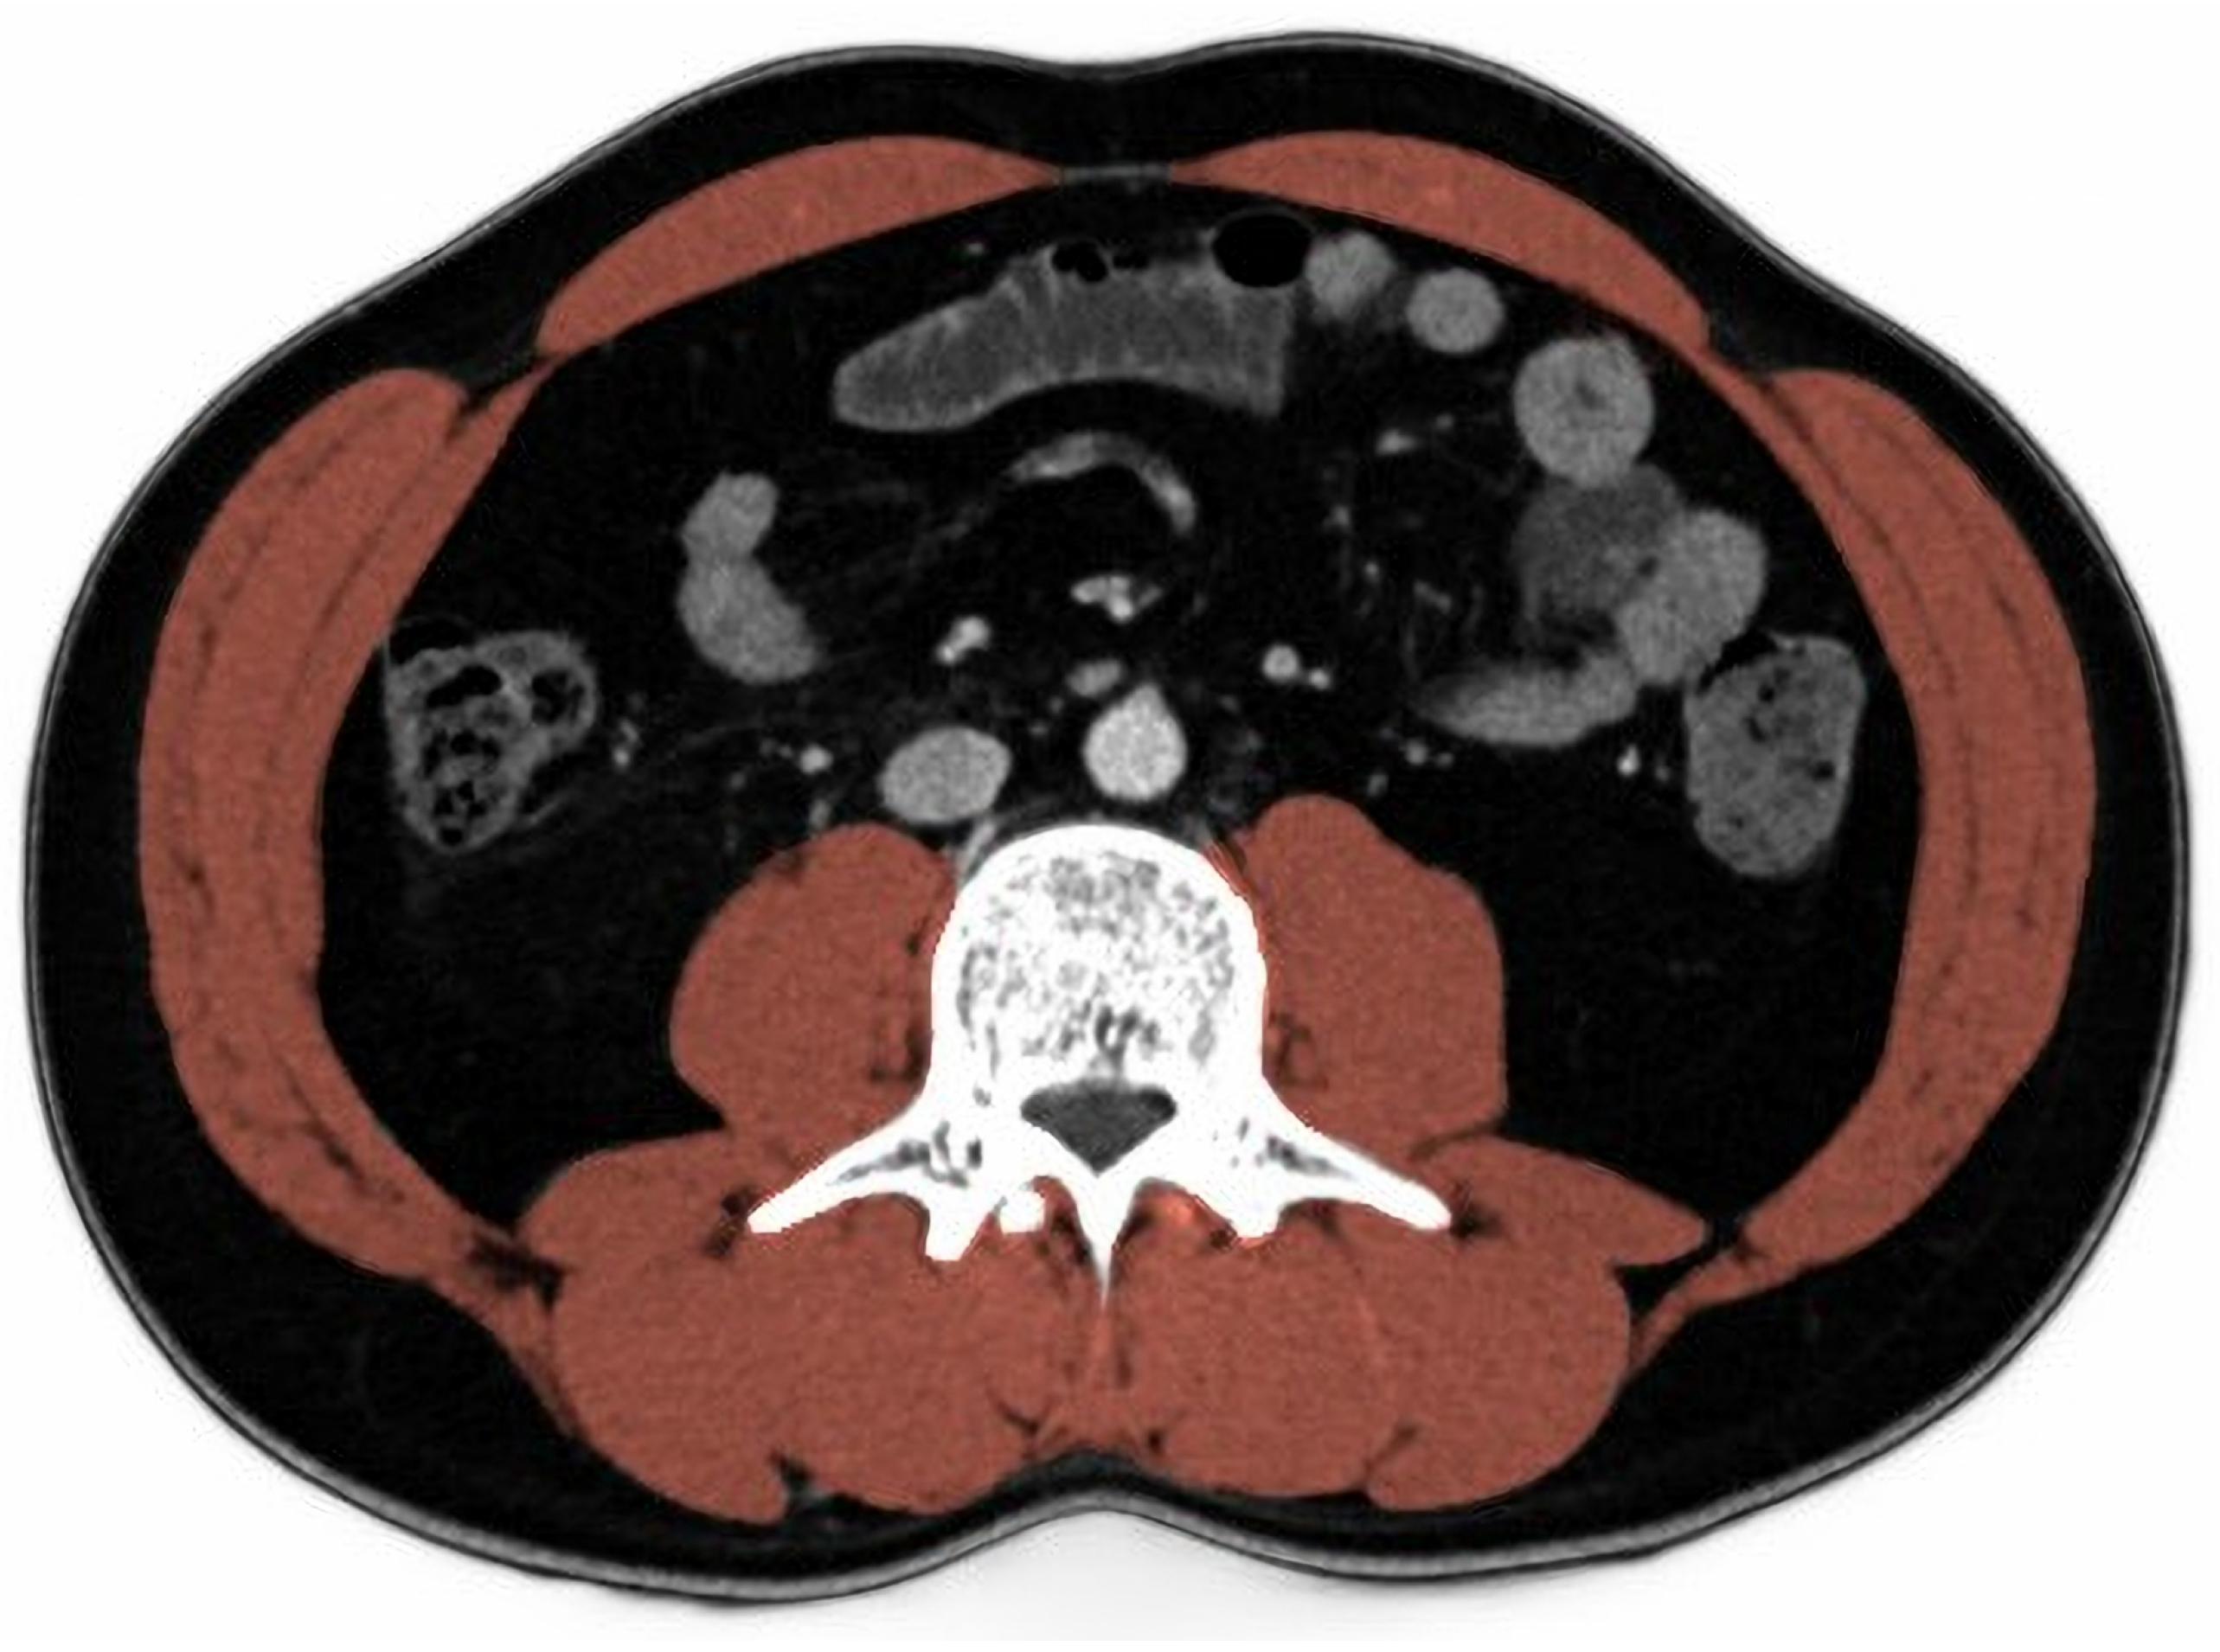

2.4. Skeletal Muscle Index

- Gomez-Perez, S.; McKeever, L.; Sheean, P. Tutorial: A Step-by-Step Guide (Version 2.0) for Measuring Abdominal Circumference and Skeletal Muscle from a Single Cross-Sectional Computed-Tomography Image Using the National Institutes of Health ImageJ. JPEN J. Parenter. Enter. Nutr. 2020, 44, 419–424. [Google Scholar] [CrossRef]

- Gomez-Perez, S.L.; Haus, J.M.; Sheean, P.; Patel, B.; Mar, W.; Chaudhry, V.; McKeever, L.; Braunschweig, C. Measuring Abdominal Circumference and Skeletal Muscle from a Single Cross-Sectional Computed Tomography Image: A Step-by-Step Guide for Clinicians Using National Institutes of Health ImageJ. JPEN J. Parenter. Enter. Nutr. 2016, 40, 308–318. [Google Scholar] [CrossRef]

- Mourtzakis, M.; Prado, C.M.; Lieffers, J.R.; Reiman, T.; McCargar, L.J.; Baracos, V.E. A practical and precise approach to quantification of body composition in cancer patients using computed tomography images acquired during routine care. Appl. Physiol. Nutr. Metab. 2008, 33, 997–1006. [Google Scholar] [CrossRef]